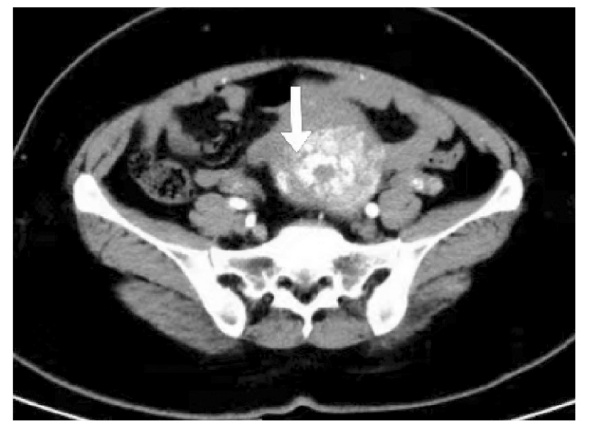

先天性心脏病术后稽留流产术中急性失血性休克属于妇产科与心血管科交叉的罕见疑难并发症,需兼顾先天性心脏病患者的特殊生理状态与稽留流产的病理特征。报告1例先天性心脏病术后稽留流产术中出现急性失血性休克患者,患者在诊断性刮宫术中发生失血性休克后急诊行子宫动脉栓塞术,术后患者病情平稳后再次行超声监测下钳刮术,顺利清除宫腔残留组织。临床上对宫腔内占位性病变性质不明确者,应通过病史、影像学检查及术后病理综合分析明确诊断。罕见疑难病例诊治中需充分利用医疗资源,践行科学、合理、人性化的诊疗思路,最大限度保障患者生命安全。